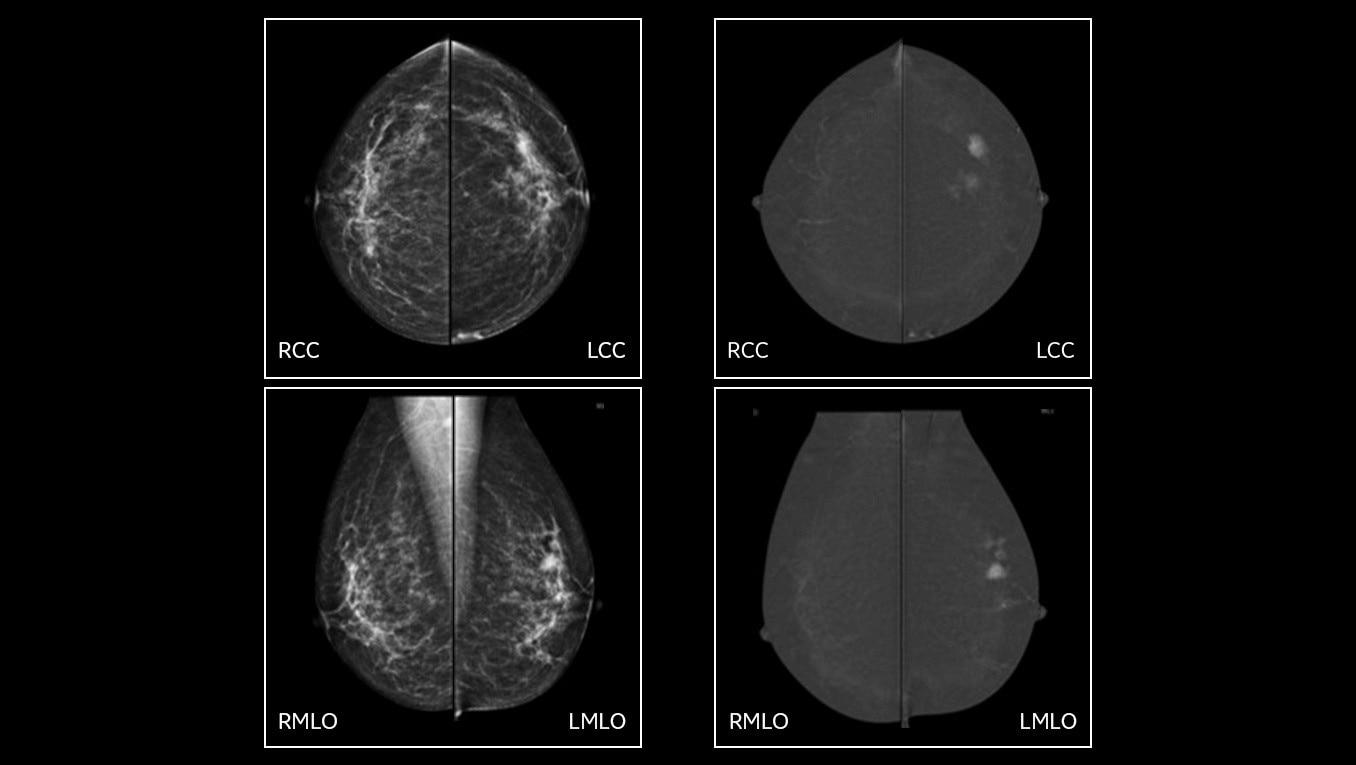

• Helps reduce the masking effect of fibroglandular breast tissue and increases the tumour signal1.

• Contrast agent highlights areas of unusual blood flow.

• Find lesions that cannot be seen on routine mammography6,7,8.

• Provide high specificity for low false-positives1.

• With Nira, overall Image quality was better assessed in more than 98% of the images presented by all the readers9.